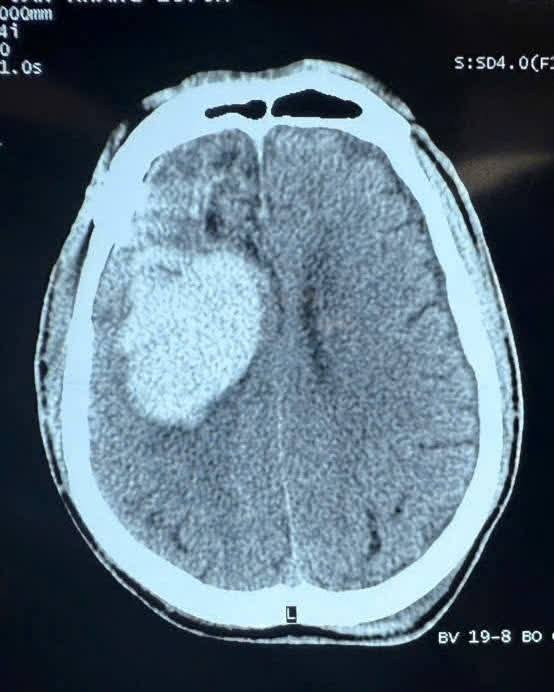

chan-tuong.jpg

Hình ảnh chấn thương não trên phim chụp - Ảnh BSCC